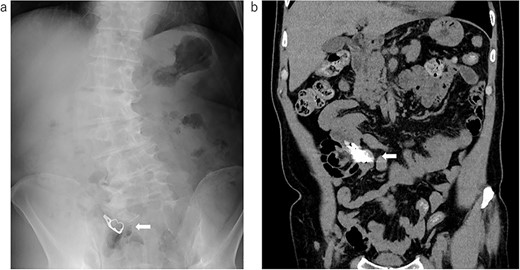

Abdominal examination findings were normal. Blood exams showed no unusual findings except slight renal dysfunction (BUN 38.2 mg/dl, Cre 1.98 mg/dl). We asked the previous doctor to provide the results of the imaging test (Fig. 1a and b). After that, we performed X-ray (Fig. 2a) and CT (Fig. 2b) examinations at our hospital and confirmed that the denture was still in the small intestine. Since it remained in the intestinal tract for a long time, there was no possibility of spontaneous excretion. Although the patient was asymptomatic, we decided to perform surgery because the patient himself wanted to have it removed.

The image data were obtained at our hospital; (a) X-ray examination: the arrow shows the swallowed denture; (b) the coronal image of the CT: the arrow shows the swallowed denture.